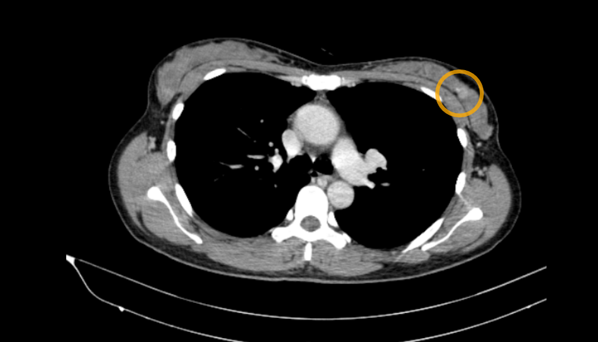

Hình 3. Hình ảnh CT lồng ngực: Ổ ngấm thuốc kém vú trái (vòng tròn vàng)

– Chụp cắt lớp vi tính ngực: Nốt bán đặc thùy dưới phổi phải ~6mm, các ổ ngấm thuốc kém hai vú, kích thước ~14x11mm